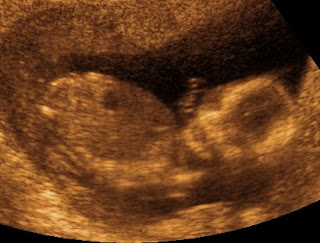

Here is a picture of her laying on her back looking at the camera (her head is on the right).

In this one, she is laying on her back sucking her thumb (head on the left).

This one is my favorite. It shows her sucking her thumb in 4d (head on the top right).